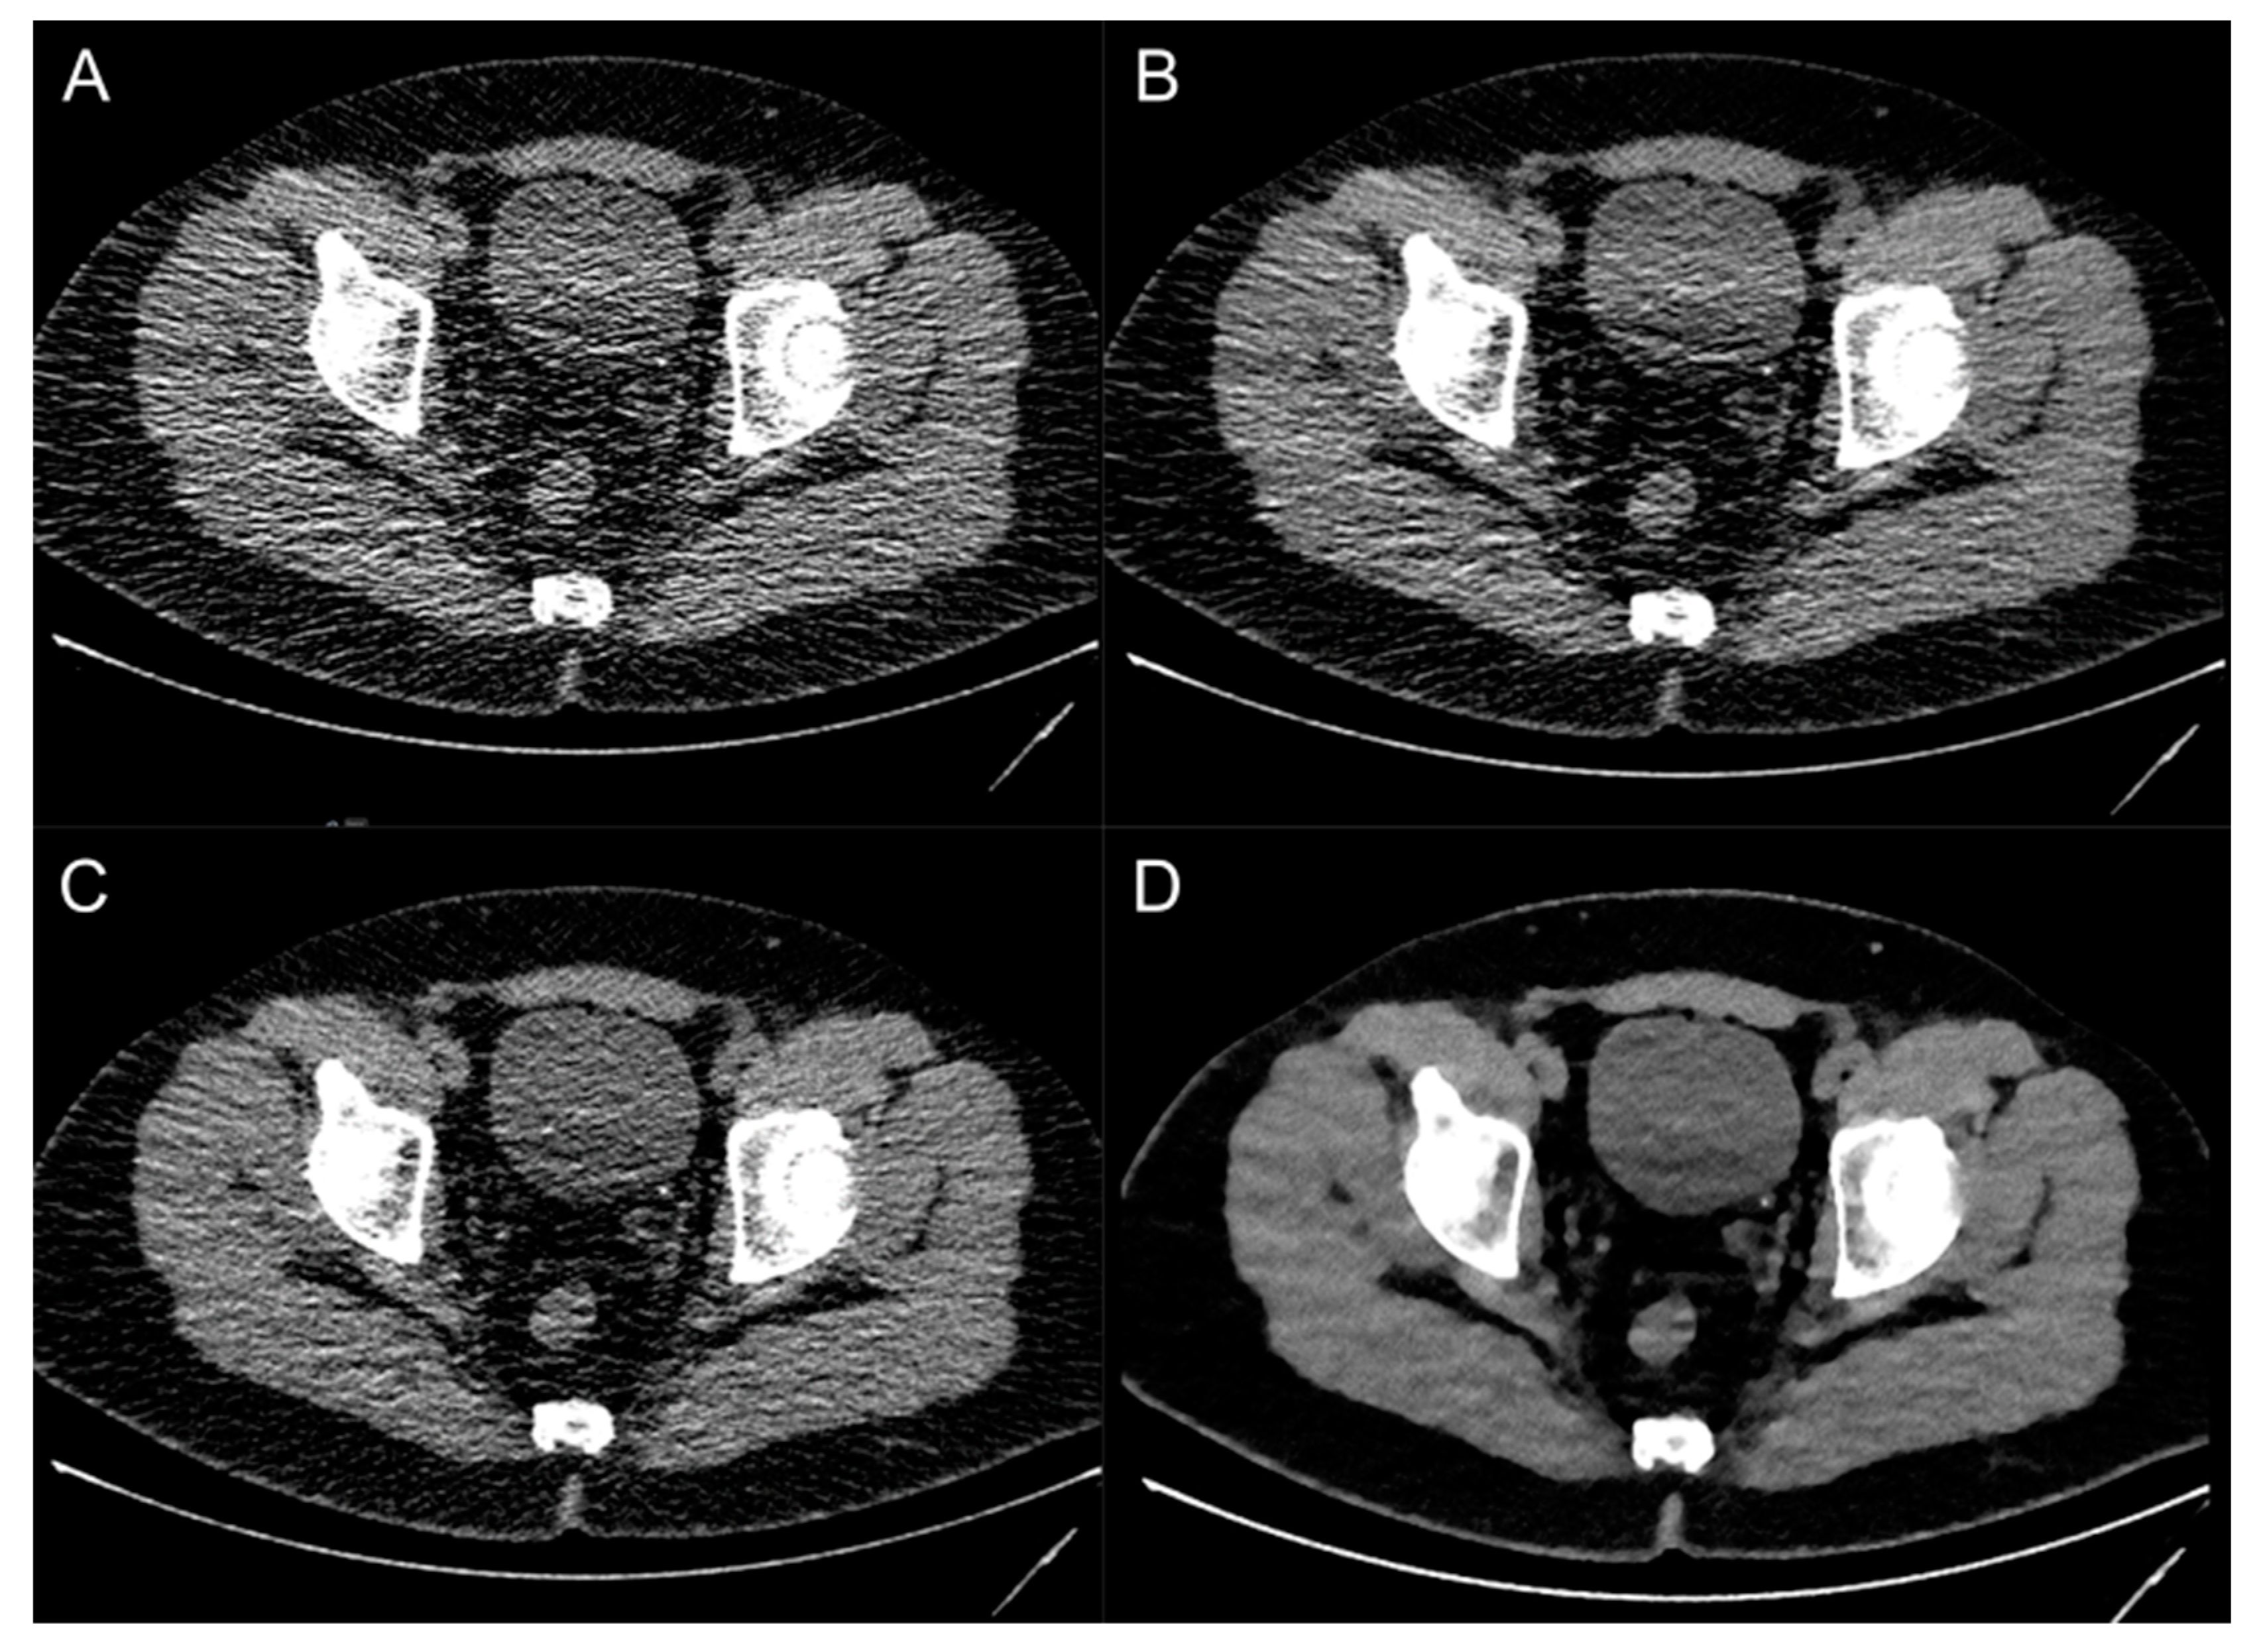

Image Quality

| Image noise | 2 (1–2) | 3 (2–3) | 4 (4–5) | 3 (2–3) |

| Overall image quality | 2 (2–3) | 3 (3–3) | 4 (4–4) | 3 (3–3) |

| Delineation of ureters | 2 (2–3) | 3 (2–3) | 4 (3–4) | 3 (2–3) |